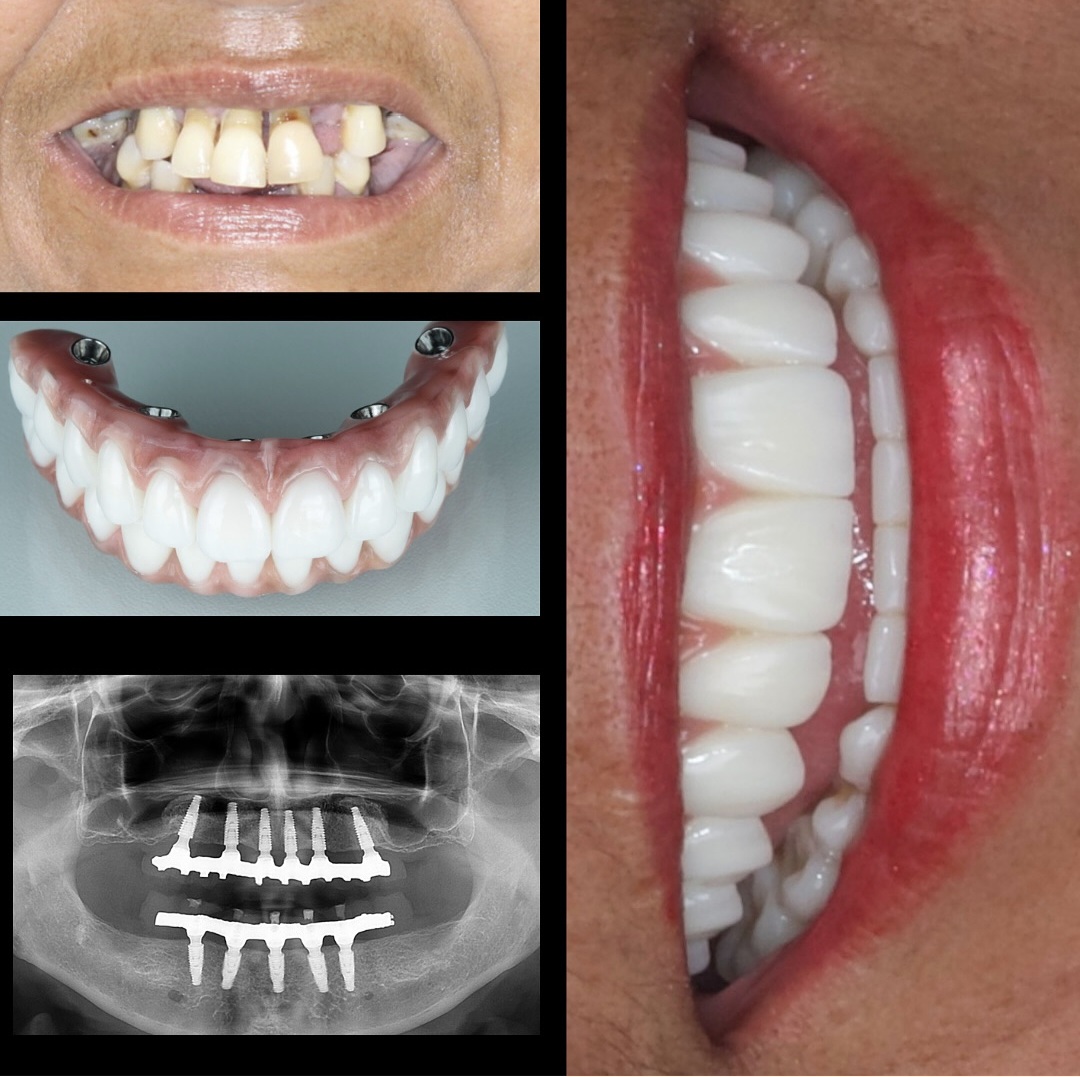

Uma solução fixa e definitiva para quem perdeu vários ou todos os dentes, oferecendo segurança, conforto e qualidade de vida.

É uma técnica que utiliza vários implantes conectados entre si para suportar uma prótese fixa completa (superior ou inferior). É a solução ideal para quem perdeu todos os dentes ou usa dentadura solta.

Sim. Tanto o formato quanto a cor são planejados para harmonizar com o rosto do paciente. Além disso, a fixação nos implantes proporciona mais firmeza e segurança ao morder e sorrir.